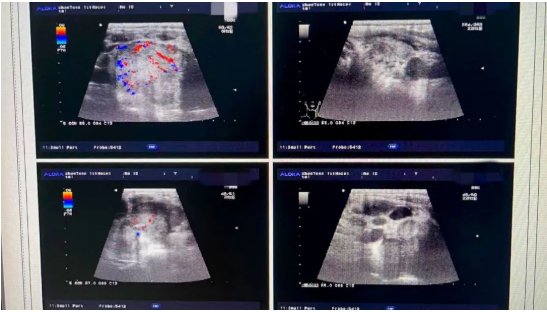

该患者入院时主诉为颈部增粗,感呼吸及吞咽不适就诊,当时门诊完善甲状腺超声检查后以“双侧甲状腺结节性质待定”收住普外一科,因遵循术前诊断、术后明确诊断原则,遂进行多学科会诊协作。

该患者随后由内分泌科行术前诊断,具体为再次对该患者进行甲状腺超声评估。针对患者病情,内分泌科麦文才副主任医师对该患者进行甲状腺结节超声引导下细针穿刺行甲状腺结节细胞学检查,标本由病理科主治医师申会秀进行细胞学检查,以期精准诊断。

结果甲状腺细针穿刺病理结果明确诊断考虑:甲状腺未分化癌。